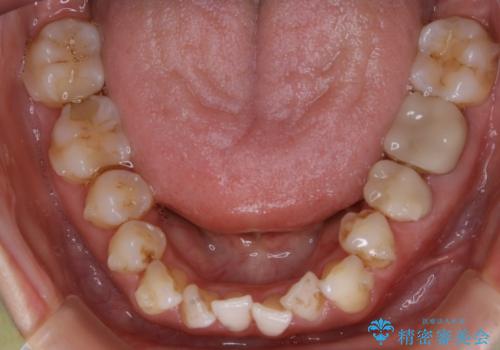

- 歯のガタつきによる見栄えや清掃困難を主訴にご来院されました。

左側の噛み合わせは上の歯が前方に寄ってきてしまっていることが原因のズレがありました。

ガタつき自体は歯列の幅の拡大やディスキング(IPR)でほとんど解消可能でしたが、噛み合わせのズレは歯の移動が必要だったため、左上にマイクロインプラントを使用し噛み合わせの改善とガタつきの解消を同時に進めるという方針をとりました。

ディスキング(IPR)

歯のガタつきをとるためのスペース作りの方法の一つにディスキング(IPR)という方法があります。

歯と歯の間を一ケ所あたり最大0.5mmまでの範囲内で削ることで歯自体が少し小さくなり、それにより作られるスペースを数ヶ所分合わせることで合計で数mmの大きなスペースが作れるという方法です。

当院ではなるべく歯の機能や見た目に影響の出ないよう、作業時に拡大鏡の使用や削るタイミングの微調整を行っています。